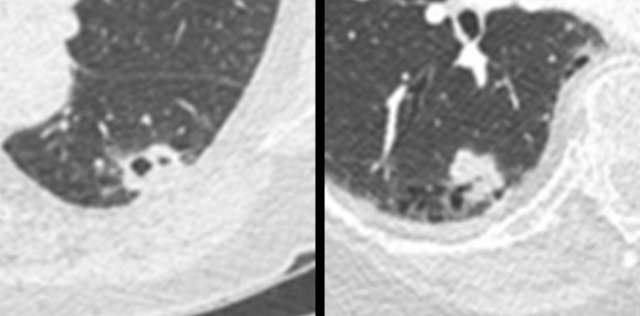

The images show a small cystic precursor lesion (left panel) initially interpreted as “thin-walled cavity, likely infection”.

The next CT was obtained for cough 4 years later, showing a T4 squamous cell carcinoma (right panel).

Patient was alive 2 years after resection and systemic treatment.